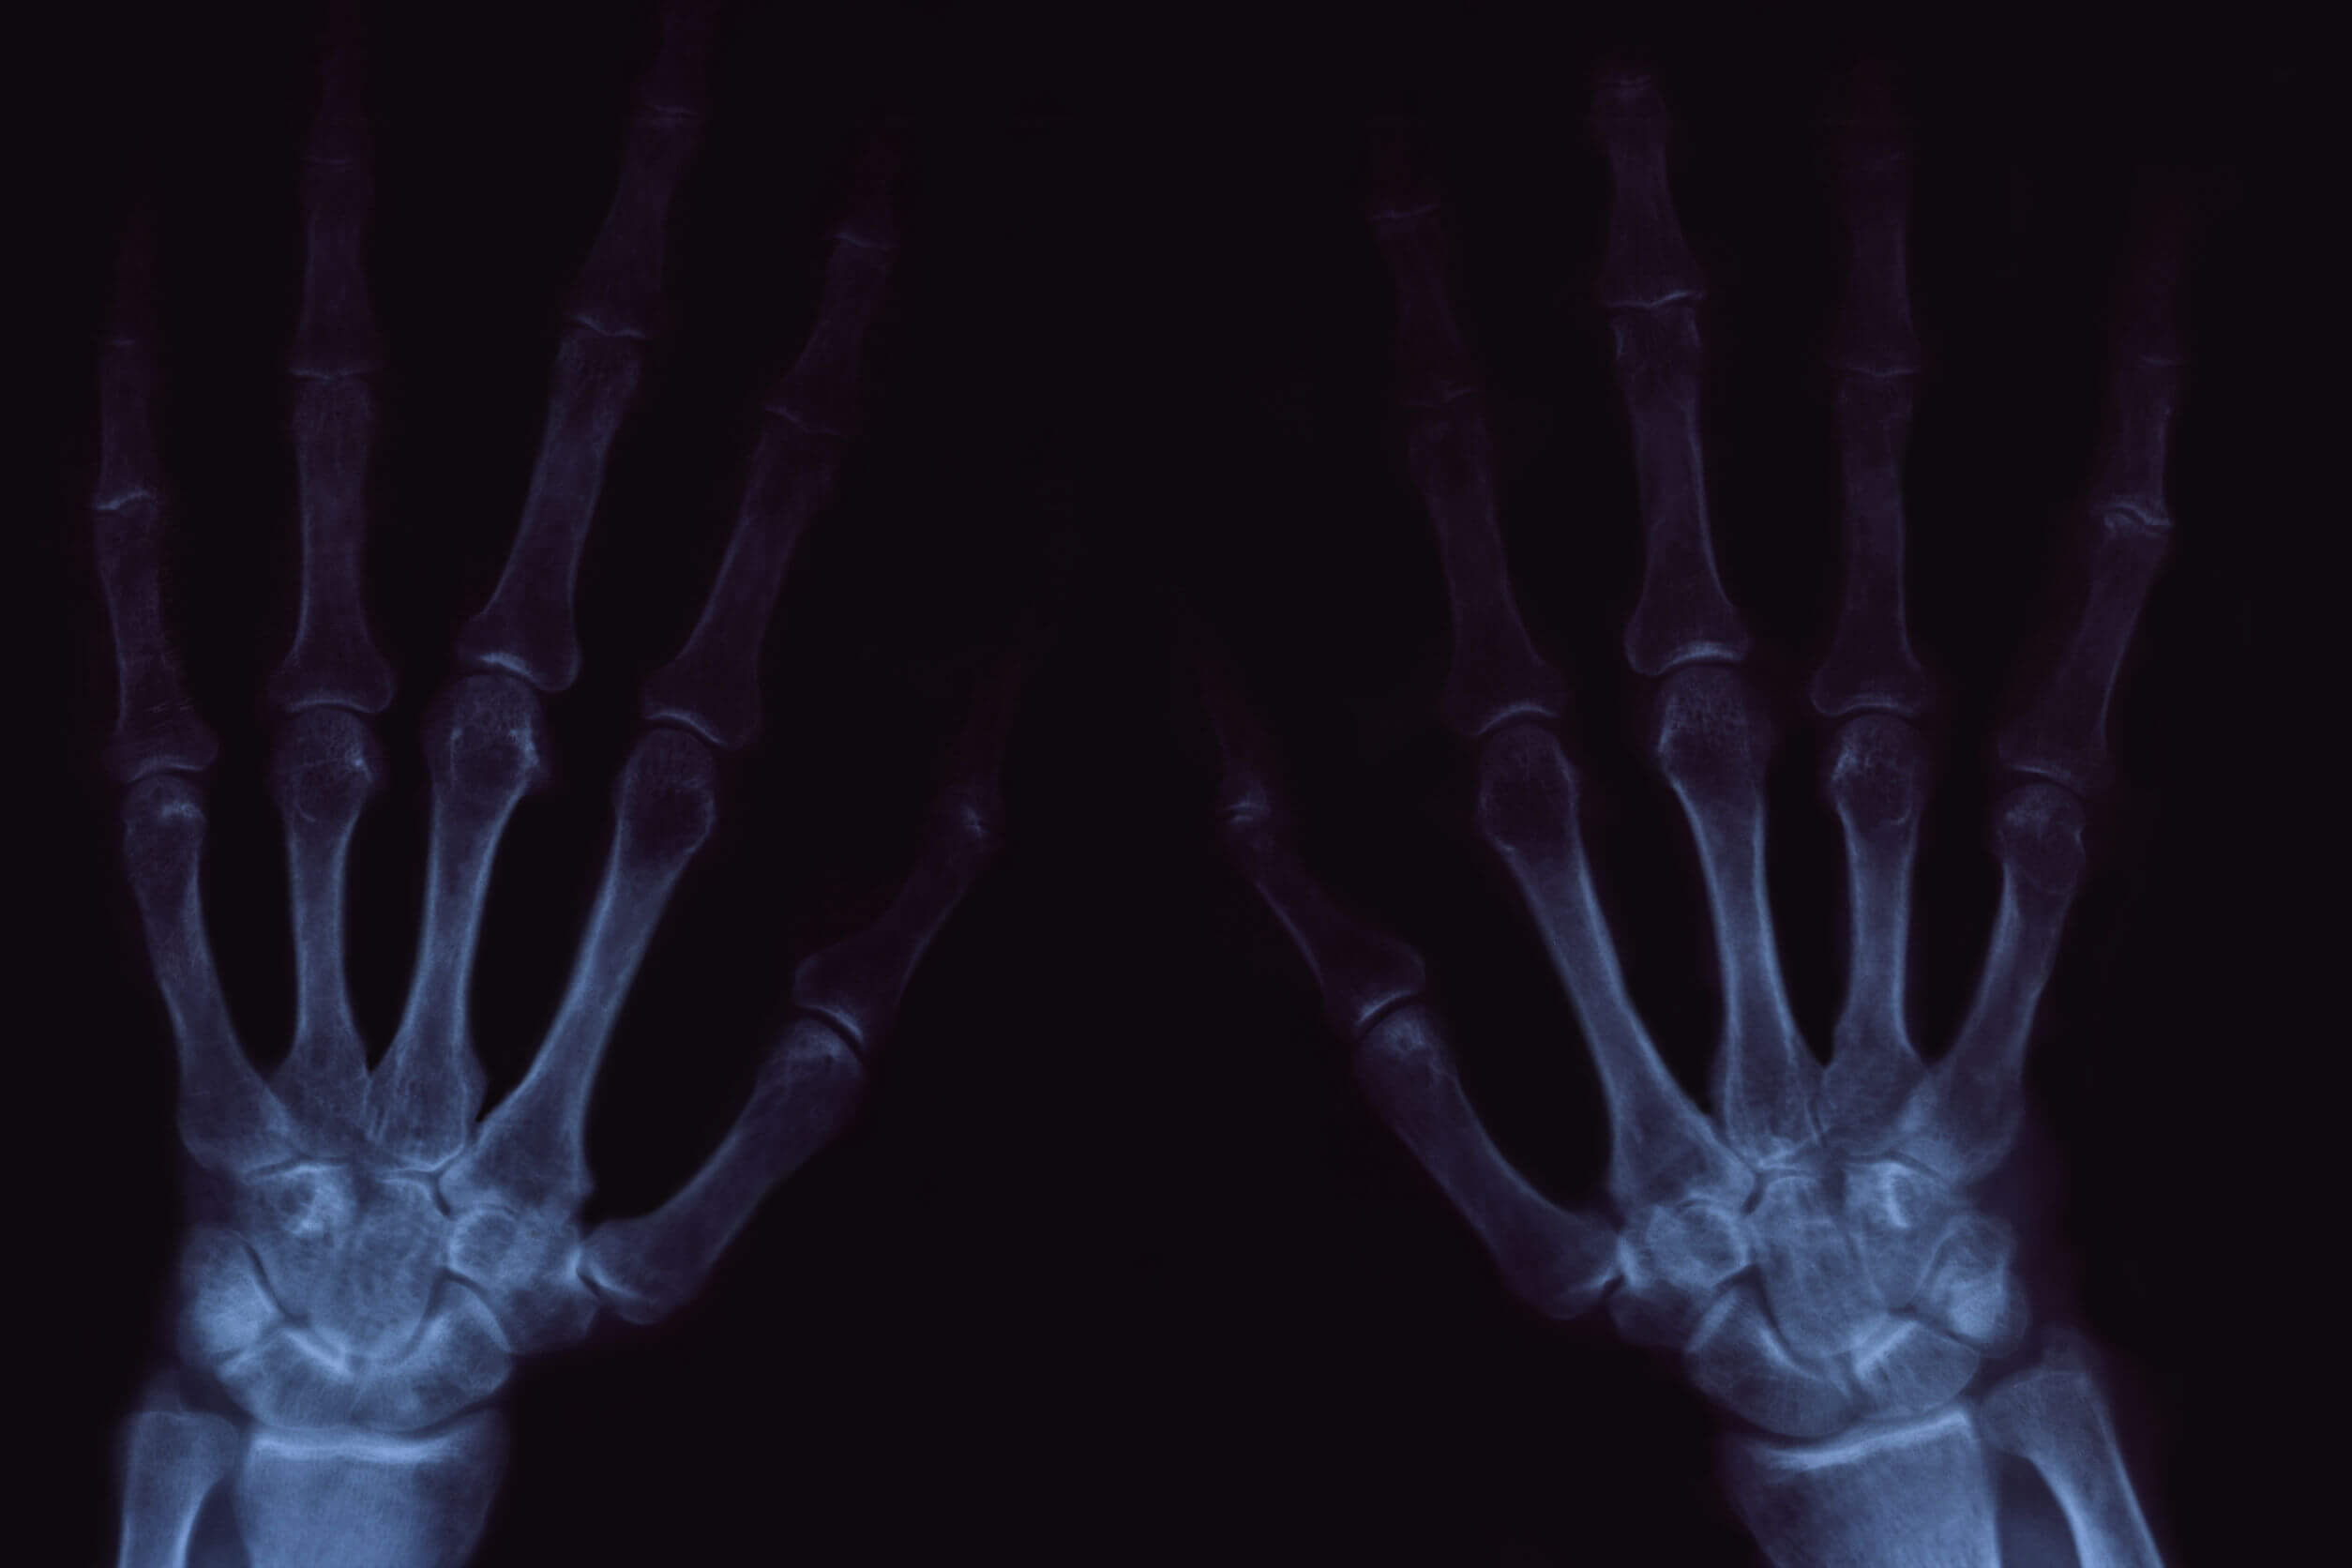

A nivel radiológico, es posible evidenciar algunas estructuras llamadas osteofitos, unas protuberancias óseas que suelen desarrollarse en los extremos de los huesos.

Sinovitis y el crujido de las articulaciones

Se trata de la inflamación de la membrana sinovial. Puede ocurrir de forma aislada o como resultado de otras patologías inflamatorias en la misma área, como la artritis reumatoide. Se caracteriza por la aparición de dolor abrupto y aumento de volumen en la articulación afectada.

Otras enfermedades que pueden acompañarse de una sinovitis son la tendinitis (que en su conjunto se conocen como tenosinovitis), la gota, el lupus y la misma artrosis que comentamos en el apartado anterior.